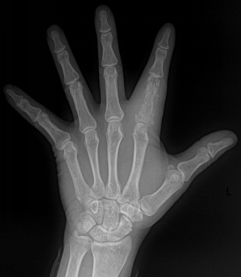

多指畸形

手足短骨解剖及常见疾病的影像学表现